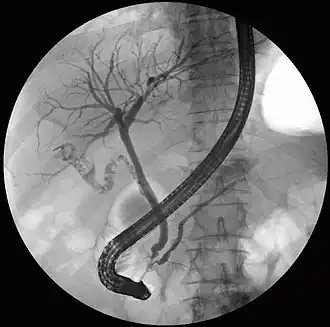

The pancreatic duct or duct of Wirsung (also, the major pancreatic duct due to the existence of an accessory pancreatic duct) is a duct joining the pancreas to the common bile duct. This supplies it with pancreatic juice from the exocrine pancreas, which aids in digestion.

The pancreatic duct joins the common bile duct just prior to the ampulla of Vater, after which both ducts perforate the medial side of the second portion of the duodenum at the major duodenal papilla. There are many anatomical variants reported, but these are quite rare.[2]

Most people have just one pancreatic duct. However, some have an additional accessory pancreatic duct, also called the Duct of Santorini. An accessory pancreatic duct can be functional or non-functional.[3][4] It may open separately into the second part of the duodenum,[3][4] which is dorsal, and usually (in 70% of people) drains into the duodenum via the minor duodenal papilla. In the other 30% of people, it drains into the main pancreatic duct, which drains into the duodenum via the major duodenal papilla. The main pancreatic duct and the accessory duct both eventually—either directly or indirectly—connect to the second part ('D2', the vertical segment) of the duodenum.

Compression, obstruction or inflammation of the pancreatic duct may lead to acute pancreatitis. The most common cause for obstruction is the presence of gallstones in the common bile duct, a condition called choledocholithiasis. Obstruction can also be due to duodenal inflammation in Crohn's disease.[7] A gallstone may get lodged in the constricted distal end of the ampulla of Vater, where it blocks the flow of both bile and pancreatic juice into the duodenum. Bile backing up into the pancreatic duct may initiate pancreatitis.[8] The pancreatic duct is generally regarded as abnormally enlarged if being over 3 mm in the head and 2 mm in the body or tail on CT scan.[9] Pancreatic duct or parts of pancreatic duct can be demonstrated on ultrasound in 75 to 85% of people.[10]